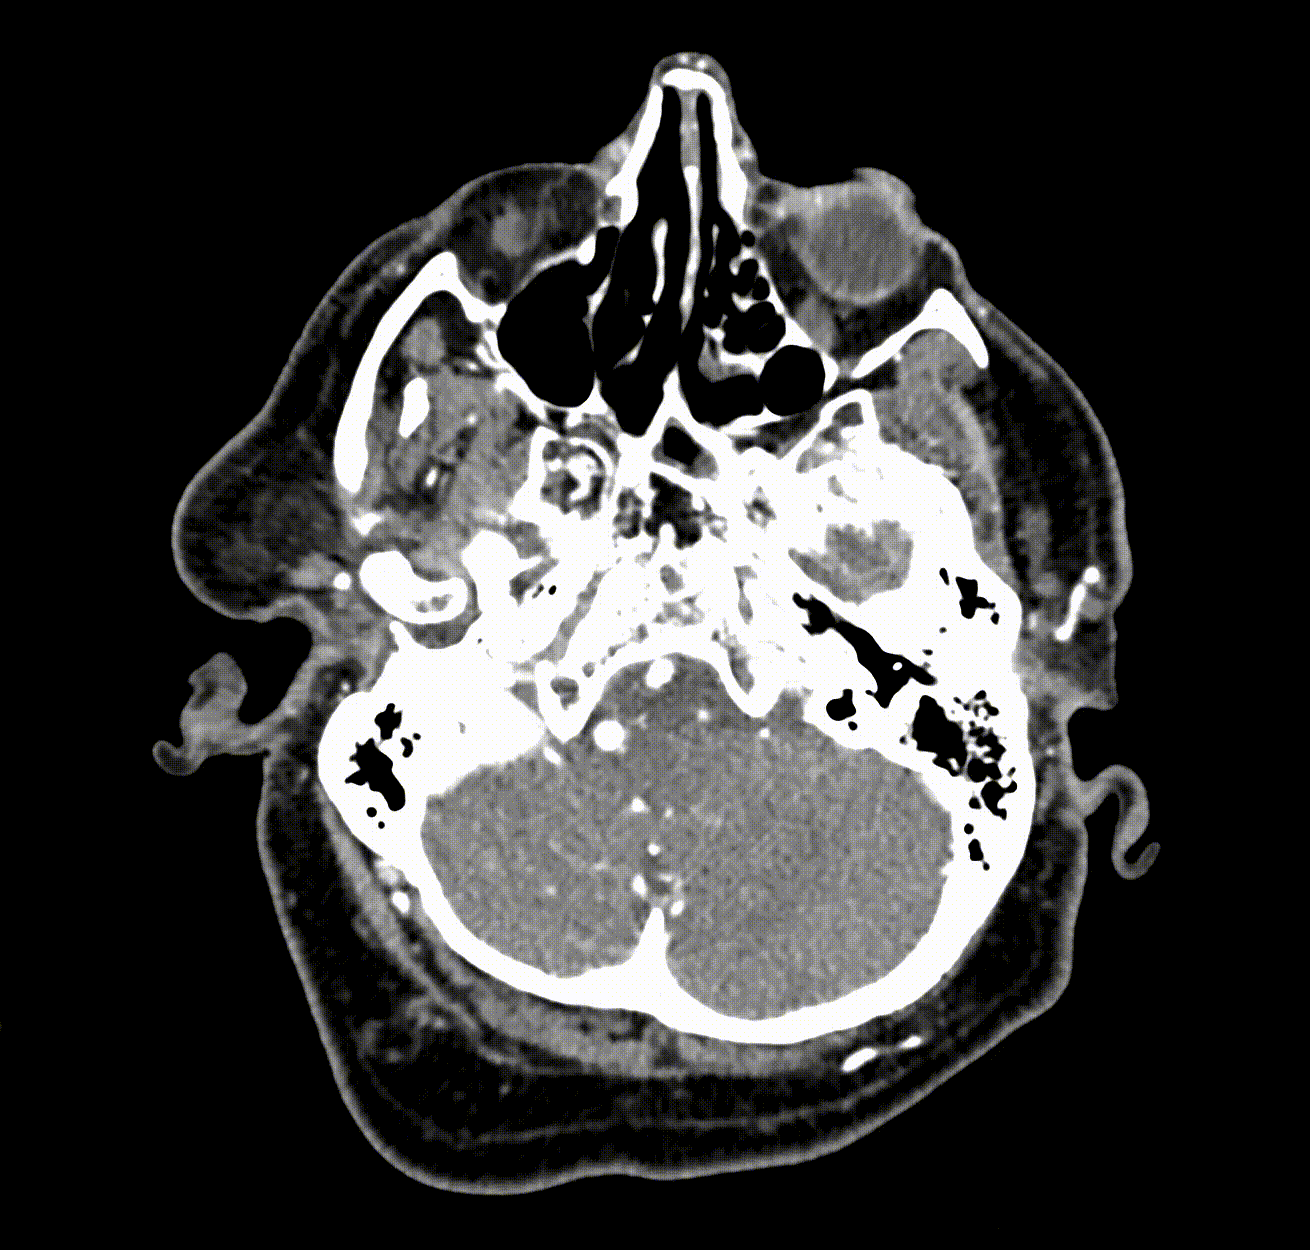

Image credit: Allison Park (Stanford)

The complications with the diagnostic process created unique challenges for Yeom and her team when approaching the creation of their AI tool HeadXNet. The importance of avoiding misdiagnosis meant that HeadXNet couldn’t provide excessive influence over a doctor’s decisions. Furthermore, brain scans are full three-dimensional models with much more complexity than the flat images that convolutional neural networks are typically trained to understand. To address these problems, Yeom’s team manually labeled every in the training data to specify whether it contained an aneurysm. After training, HeadXNet only provided its response in the form of an overlay to pinpoint locations in the brain with the highest probability of an aneurysm without providing further influence that could influence a misdiagnosis.